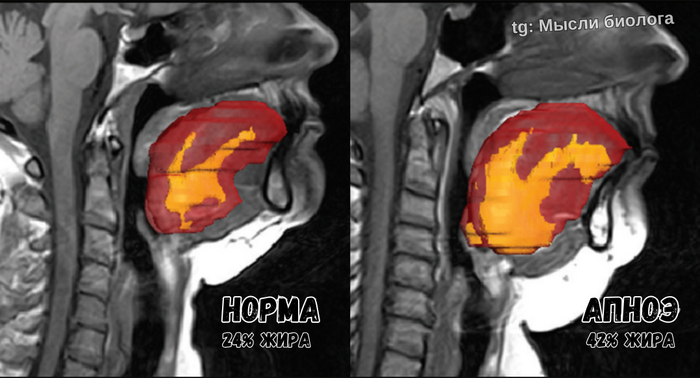

Наш организм умеет запасать жир не только на животе и боках, но и в тканях языка. А чем больше объём языка, тем выше риск того, что во сне он будет перекрывать дыхательные пути и приводить к апноэ.

На картинке с МРТ отлично видно разницу в уровне жира и размере языка, а также механику процесса.